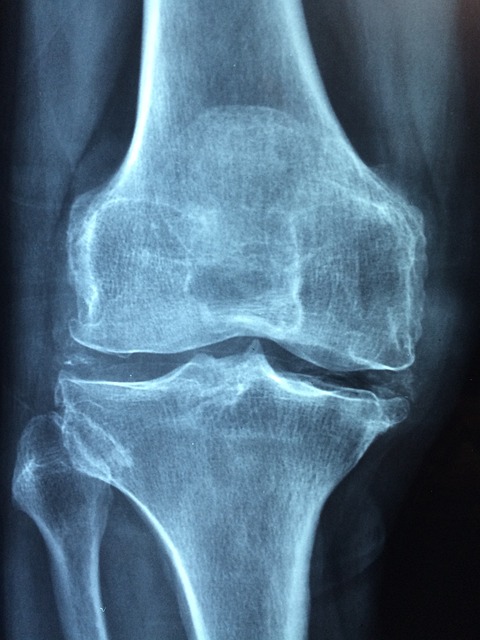

무브프리 효능 중 가장 주목할 만한 것은 관절 통증을 완화하는 효과입니다. 무브프리의 주요 성분인 글루코사민과 콘드로이틴은 관절 통증을 완화하는 데 도움을 줍니다. 이들 성분은 연골의 주요 구성 요소로, 관절의 마찰을 줄이고 통증을 감소시킵니다. 무브프리를 꾸준히 복용하면 일상 생활에서의 관절 통증이 눈에 띄게 줄어듭니다. - 연골 보호 및 재생

무브프리 효능 중 또 다른 중요한 점은 연골 보호 및 재생 효과입니다. 글루코사민은 연골 세포의 합성을 촉진하고, 콘드로이틴은 연골의 분해를 억제하여 연골 보호 및 재생에 기여합니다. 이를 통해 무브프리는 관절의 퇴화를 방지하고 건강한 상태를 유지하는 데 도움을 줍니다. 특히, 무브프리 효능을 통해 연골 손상을 예방하고, 이미 손상된 연골을 회복하는 데 효과적입니다. - 관절의 유연성 및 이동성 향상

무브프리 효능 중 항염 작용은 관절염으로 인한 붓기와 통증을 완화하는 데 효과적입니다. 무브프리의 성분들은 항염 작용을 통해 관절 염증을 줄여줍니다. 이는 장기적으로 관절의 건강을 유지하고, 관절염으로 인한 불편함을 줄이는 데 큰 도움이 됩니다.